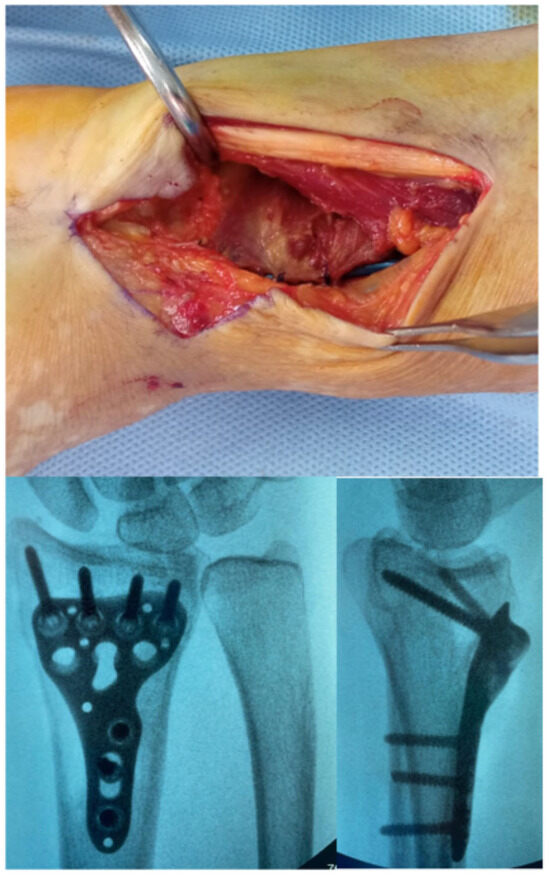

Introduction: Lateral epicondylitis (LE) typically affects the extensor carpi radialis brevis (ECRB) tendon, while isolated degeneration of the extensor digitorum communis (EDC) origin is rare and poorly characterized. Surgical debridement of these lesions may result in capsular exposure requiring soft-tissue coverage, which can

Introduction: Lateral epicondylitis (LE) typically affects the extensor carpi radialis brevis (ECRB) tendon, while isolated degeneration of the extensor digitorum communis (EDC) origin is rare and poorly characterized. Surgical debridement of these lesions may result in capsular exposure requiring soft-tissue coverage, which can be achieved through a vascularized muscle flap to enhance tendon healing potential and reduce recurrence. This study aimed to describe a modification of the anconeus rotation flap as originally described by Almquist in 1998, and to evaluate its clinical and functional outcomes in patients with isolated EDC tendinopathy. The modified technique consists of a simpler muscle advancement (AMA) that preserves the distal vascular pedicle and reduces soft-tissue dissection. Methods: A retrospective study was conducted on 12 consecutive patients with lateral epicondylitis with isolated EDC tendon involvement (10.71% of all operative cases at our Institution between 2019 and 2022), who were surgically treated with the anconeus muscle advancement modification. Clinical outcomes, including the visual analog pain scale (VAS), grip strength and patient-reported outcome measures (PROMs), which include the QuickDASH score, the Mayo Elbow Performance Score (MEPS) and the Patient-Rated Tennis Elbow Evaluation (PRTEE) score were assessed. Paired statistical tests with 95% confidence intervals and minimal clinically important difference (MCID) thresholds were applied. Results: At a mean follow-up of 38 months, all outcomes demonstrated statistically significant and clinically meaningful improvements (p < 0.05). Reductions in pain/disability (VAS, QuickDASH, PRTEE scores) and functional gains (Grip strength, MEPS) far exceeded their respective MCID thresholds, with 100% attainment for each outcome. Conclusions: This modified anconeus muscle advancement appears to be a technically feasible option for managing isolated EDC-related lateral epicondylitis, preserving vascular integrity while limiting dissection. Although favorable results were obtained, the small retrospective cohort precludes definitive conclusions regarding efficacy. The findings support the technical feasibility of the proposed modification and warrant further prospective comparative investigations.

(This article belongs to the Special Issue Feature Papers in Hand Surgery and Research)